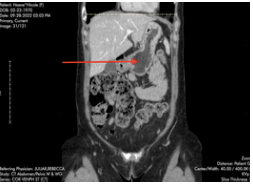

Second, (and this is where I think I might give myself a tiny little victory lap,) he compared my duodenum from a CT in 2017 to last weeks. “Look at this, it’s much more normal now – did you gain weight?” Yes, yes I did. My duodenum, which in 2017 took up a huuuuge portion of my upper right quadrant, (probably because it was pinched off further downstream at the SMA,) now appears about the size of one of my hands. Normal! It seems I may have successfully regained the fat pad which supports the SMA angle, which can pinch the duodenum when it’s too tight. Now, perhaps, I may enjoy a less painful digestive process.

Below, arrow points to duodenum in 2022

Below: My CT from Sept. ‘22

Right arrows – SMA squishing renal vein & duodenum Left arrow – MALS “situation”